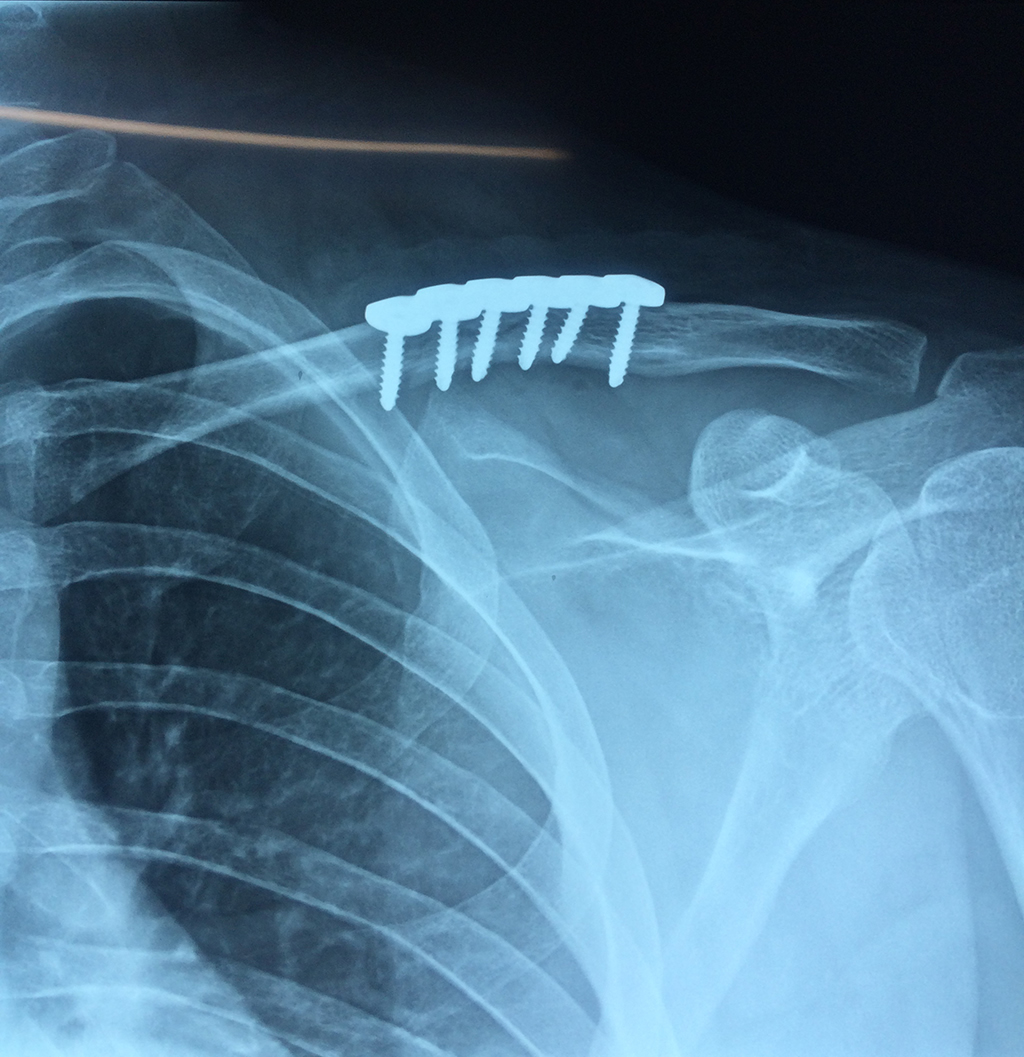

Húmero - Clavícula

La clavícula es un hueso largo, con forma de "S" itálica, situado en la parte anterosuperior del tórax. Junto con la escápula forman la cintura escapular. Se puede palpar por toda su longitud y se extiende del esternón al acromion de la escápula, siguiendo una dirección oblicua lateral y posterior.